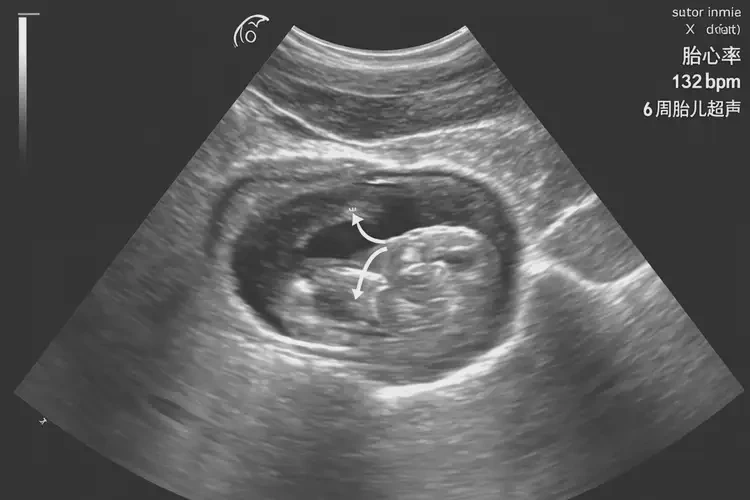

懷孕6周胎心132正常嗎

132次/分鐘

懷孕6周時(shí),胎兒的胎心率在132次/分鐘是 正常 的。胎心率是指胎兒心臟每分鐘跳動(dòng)的次數(shù),通常在懷孕6周左右,胎兒的心臟開(kāi)始形成并產(chǎn)生心跳。此時(shí),胎心率的范圍一般在 100-180次/分鐘 之間,平均值約為 130次/分鐘。